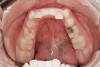

Figure 6   Continued damage from erosion produced by GERD. Other areas of erosive damage will be dictated by the sleep posture of the patient.

Figure 6